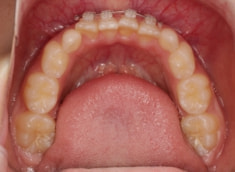

症例紹介

小児期ケース:叢生(ガタガタ)

治療法:拡大プレート+フルパッシブブラケット(クリアスナップ)

治療前